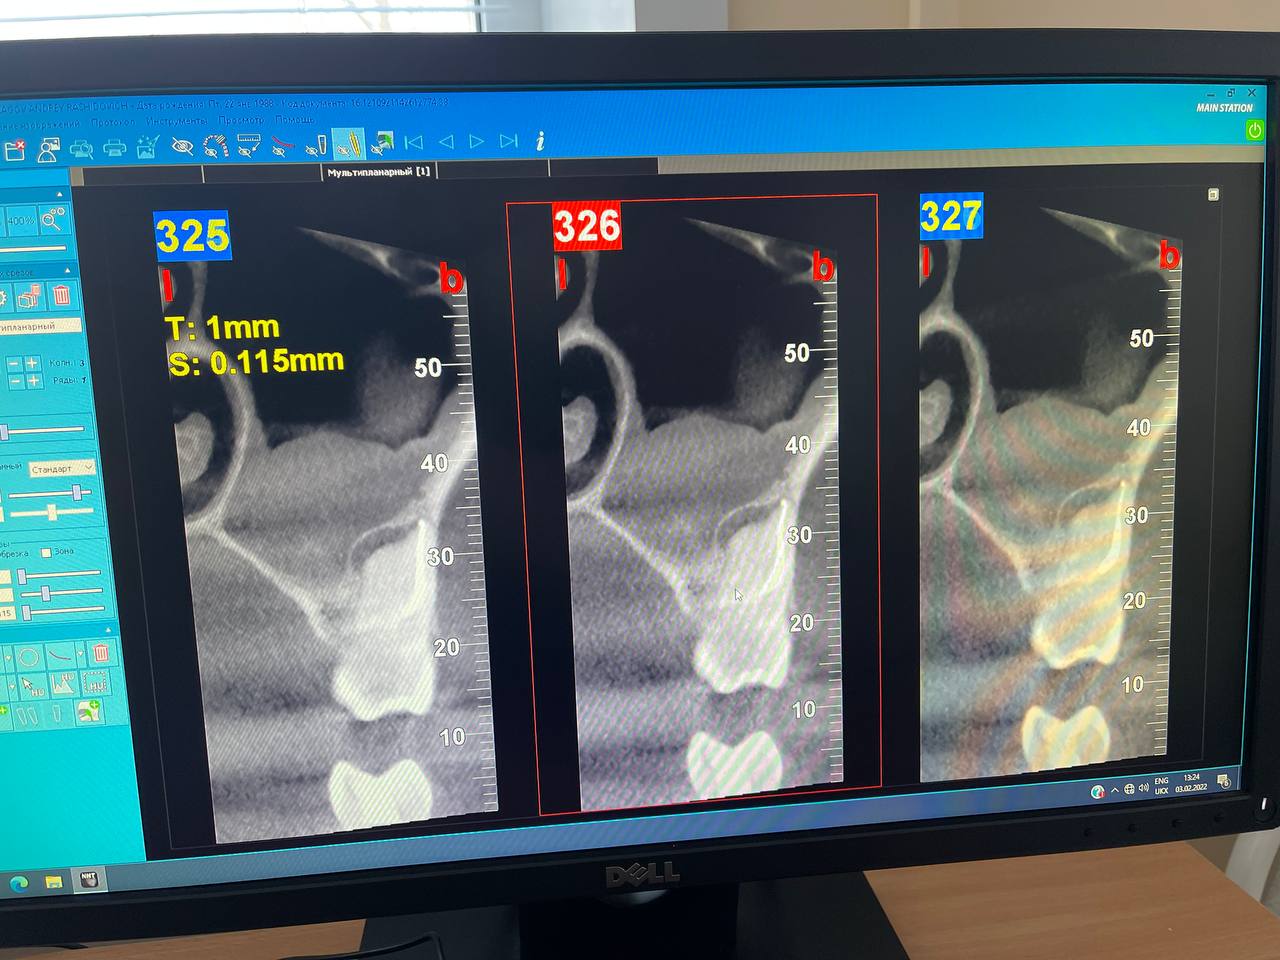

Также клиникой был выбран 3D Томограф NewTom Go. Обладает размером 10x10, что позволяет снимать две челюсти пациента, гарантированно заходят 8-ки и часть позвоночника. Доступен полный спектр ЛОР-исследований: гайморовы и лобные пазухи.